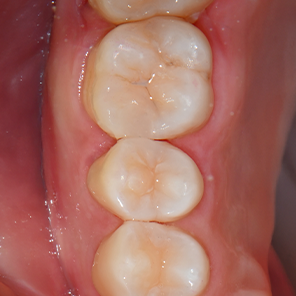

정성이 깃든

환자 한분 한분을 위한 수복

레진빌드업은 진료실 안에서 의료진의 손끝으로 완성되는 섬세한 수복 과정입니다.

환자 개개인의 치아 형태를 고려해 재료를 정교하게 쌓고, 단단히 결합되도록 마무리합니다.

연세일등치과에서는 이 모든 과정을 대표원장이 직접 진행하며, 한 분 한 분의 치아에,

대표원장의 섬세한 시선과 정성이 머뭅니다.